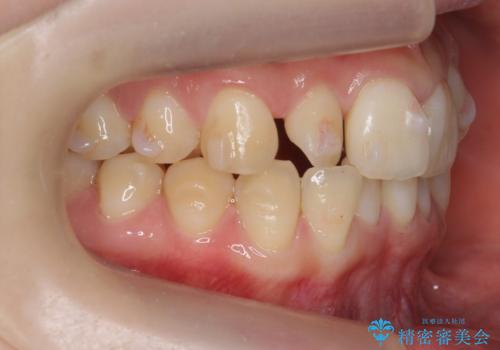

- 前歯のねじれを主訴に来院。

前から2番目の歯がねじれて下の歯の内側に入っていました。

また、奥歯のかみ合わせが上の奥歯が若干前に並んでおり、それで前歯が入りきらずにねじれていました。

歯を抜かずに奥歯を後ろに下げてマウスピースで矯正しています。

上の奥歯を後ろに下げて前歯のねじれを治すスペースを確保しました。

奥歯を後ろに下げるために、矯正用インプラントを使用しています。